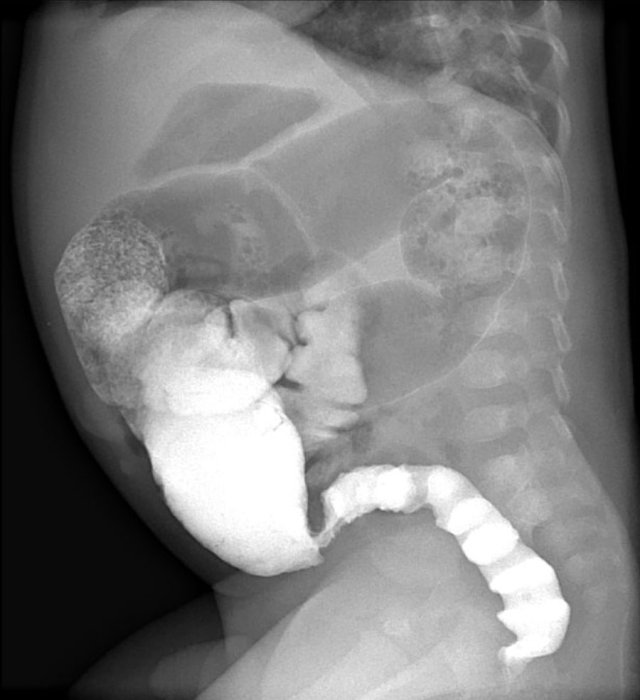

Here ultrasound images of a neonate who presented with an acute abdomen.

An ultrasound antenatally had detected a duplication cyst.

On the ultrasound there is a whirlpool sign of the vessels.

Torsion of the cyst and the mesentery had resulted in a volvulus.

This is a medical emergency and consequently the neonate went straight to the operating room.